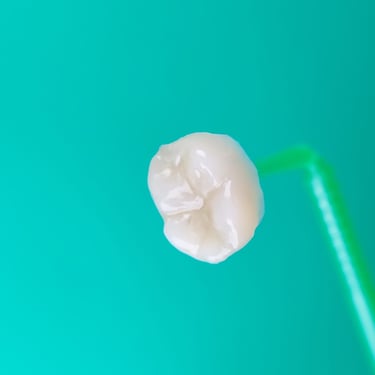

Dentes de porcelana finalizados